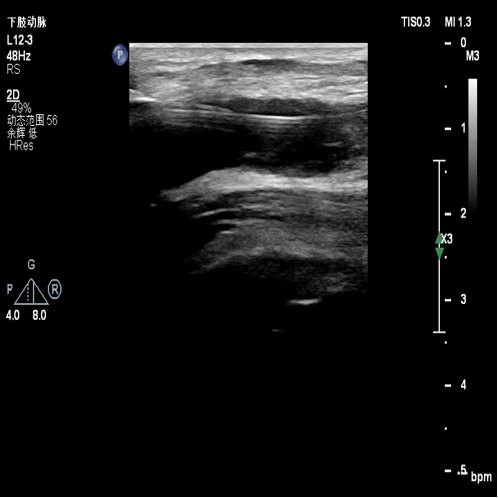

图:超声引导下导丝开通胫后动脉

图:球扩后胫后动脉

图:术前胫后动脉